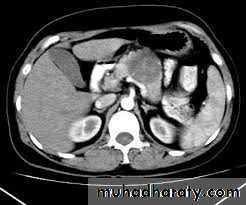

Ultrasound Scan Histology & cytology CT Scan Angiography

Approach to Investigations:

(Selective Investigations)

Ultrasound Scan

C.T. Scan MR Imaging Scan

3. Pre-operative localization of the tumour very important identification at operation can be difficult.[Combination CT Scan and selective angiography]